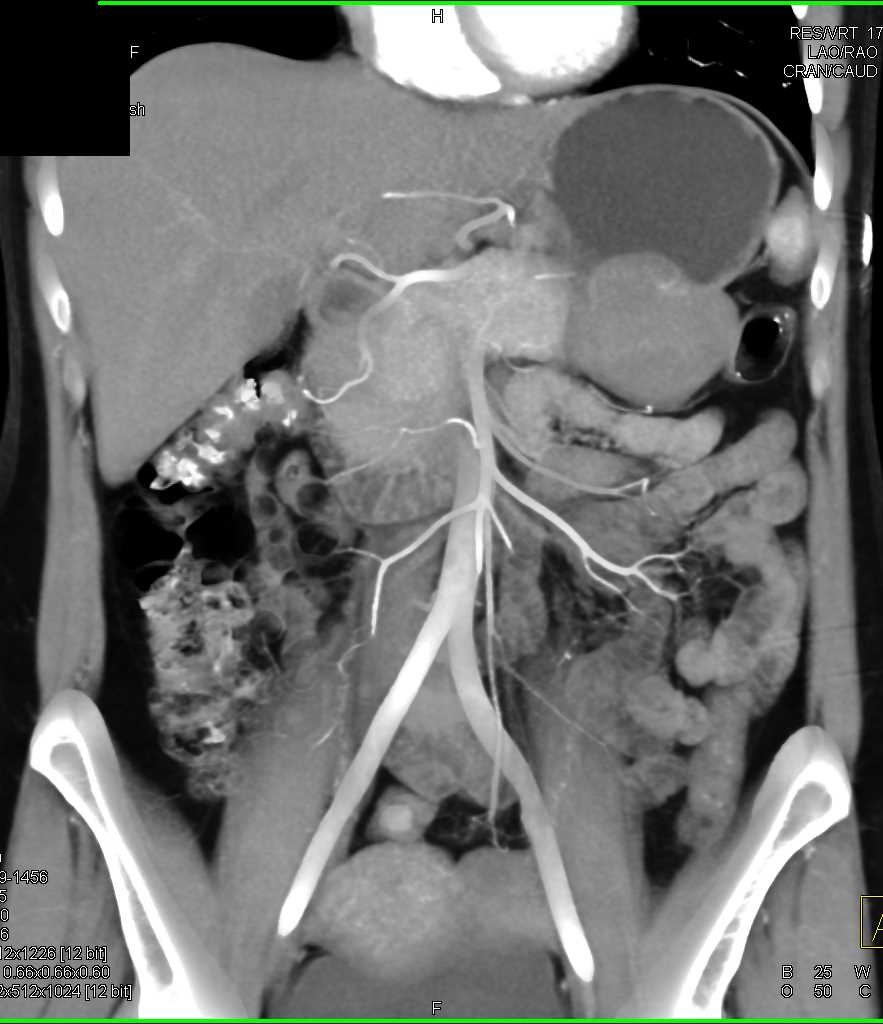

Mass Pushes on Tail of Pancreas was Ganglioneuroma